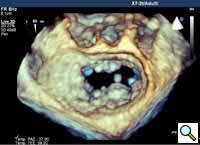

In absence of controlled clinical trial data which are forthcoming from the EVEREST II randomized study, the indications for the MitraClip therapy are currently based on registry experience and will evolve as the technique improves, experience is growing and the data to demonstrate efficacy and safety becomes available. At this time, the best indication for the MitraClip therapy is for symptomatic patients with clinically significant functional or degenerative MR who are at high or increased risk for open heart surgery. From a pure technical standpoint, the procedure so far has only been demonstrated in a subgroup of patients with specific anatomical characteristics which are summarized below and shown in Figure 3. Anatomic suitability is assessed by transesophageal echocardiography, and mitral regurgitation should originate from the central portion of the valve involving the A2-P2 segments, since the device is not ideal to work in the commissures at this time; the mechanism of MR can be either a prolapse/flail or MR due to restricted leaflet motion unrelated to rheumatic disease; the separation between the two leaflets at the site of regurgitation should be limited; severe annular dilatation and/or severe calcification should be absent or is relevant. In case of flail, the flail segment width should be less than 15 mm, and the flail gap less than 10 mm. Figure 4 is a 3D echo image of a patient with posterior leaflet prolapse selected for MitraClip therapy. In case of functional MR, the leaflets should have a minimal residual tissue available for coaptation with the MitraClip device. Figure 5 shows 2D color Doppler jet extension over the coaptation line at TEE short axis transgastric view, while Figure 6 shows the tenting area and the coaptation depth of a patient undergoing MitraClip implant.